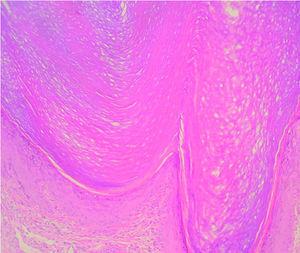

El examen dermatopatológico de una biopsia cutánea del brazo mostró hiperqueratosis ortoqueratósica e hiperplasia epidérmica con hipergranulosis (fig. 5). En cuanto al tratamiento el paciente rechazó la terapia con retinoides orales y fue tratado con emolientes y cremas de urea al 30 %, con respuesta clínica parcial. Actualmente sigue revisiones periódicas en nuestra unidad y durante 3 años de seguimiento hemos observado mejorías del cuadro ictiosiforme y de las queratosis lineales en verano, con mínima progresión del pseudoainhum.

Fig. 5.--El estudio histológico evidenció hiperqueratosis ortoqueratósica, acantosis y leve hipergranulosis. (Hematoxilina-eosina, ×400.)